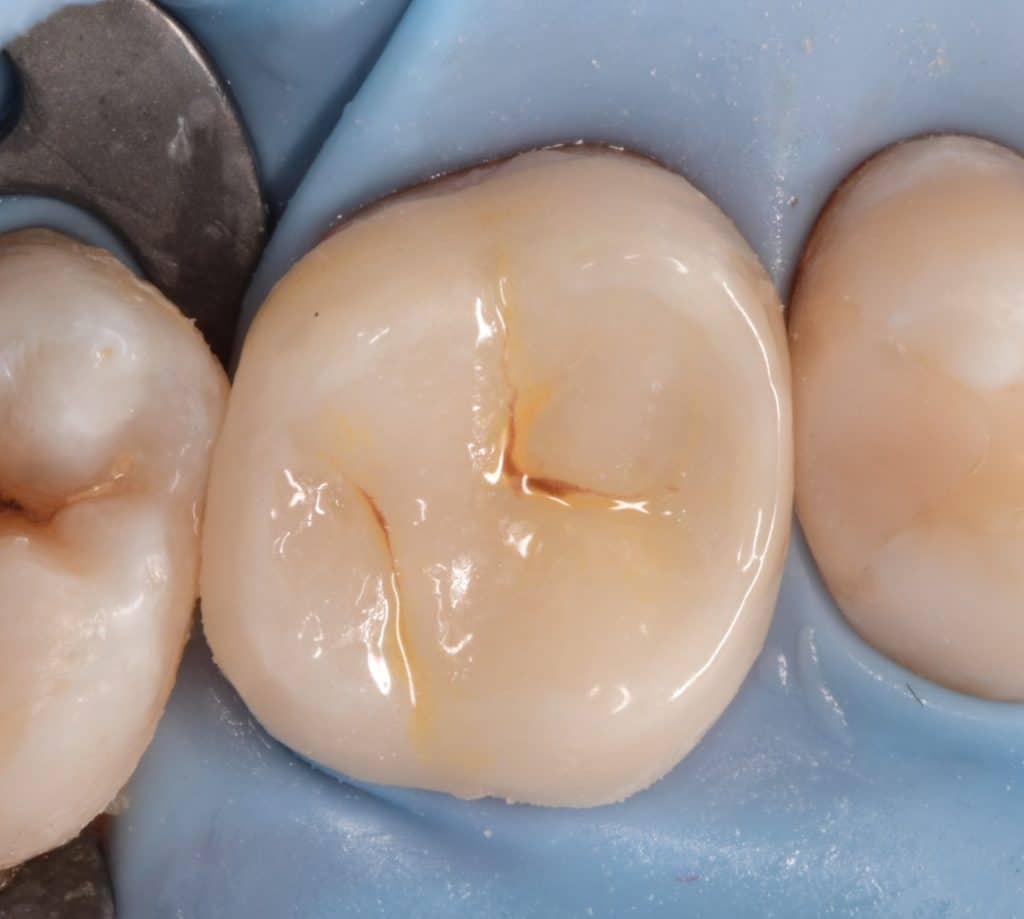

Initial situation showing large amalgam filling with open contact , the patient said that he replaced it for more than 2 times and the problem of food impaction still

Isolation with rubberdam